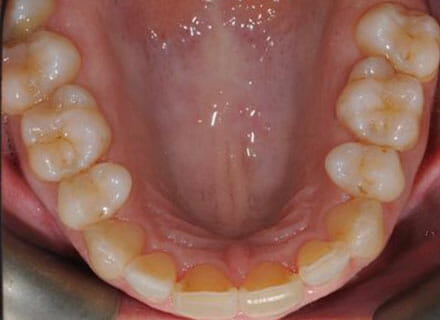

In this case, we needed to reduce the size of the central incisors as they were just too big. This combined with the crowding at the front had caused the lateral incisors to become trapped inside, pushing the big central incisor teeth forwards even more. After reducing the big teeth to a normal size we started with fixed clear bracket brace treatment and were able to complete this case in a little over a year.